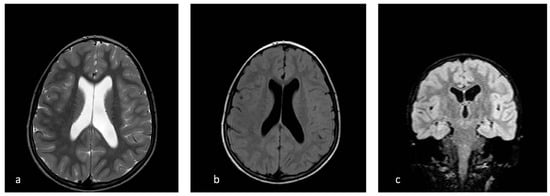

| Our patient | 46, XX, der(8)del(8)(p23.1)invdup(p12p23.1) | + | Developmental and speech delay. No meaningful sentences. Hypotonia. Hypothyroidism. Prominent forehead, arched eyebrow, thin nose with rounded tip and anteverse nostrils, flat filter, thin down-turned lips, slight micrognathia, low-set posteriorly rotated ears. Single palmar crease on the right hand and bilateral IV-V fingers clinodactyly. Hypertrichosis, previous sacrococcygeal fistula sign. Extra-rotation of the lower limbs, varus position of both the knees, flat feet. Bilateral cutaneous dimples on both elbows and knees, shield chest, inverted nipples, winged shoulder blades. Emotiveness, impulsiveness, decreased attention span. Dilatation of lateral ventricles, pineal gland’s small ectasia, moderate cystic cisterna magna’s ectasia, retrocerebellar cystic ectasia. Global chorio-retinic dystrophia, pale papilla with clear boundaries, peri-papillar pigmentary ring. Sialorrhea and extravelic palatin tonsils, ogival palate, type C tympanogram with absent stapedial reflex on the left. |